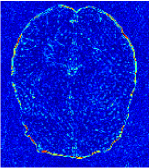

All the experiments are implemented on a Windows workstation with Intel Core i9 CPU at 3.3GHz and an Nvidia GTX-1080Ti GPU with 11GB of graphics card memory via TensorFlow Abadi et al. (2016). The parameters in the proposed network are initialized by using Xavier initialization Glorot and Bengio (2010). We trained the meta-learning network with four tasks synergistically associated with four different CS ratios: 10%, 20%, 30%, and 40%, and test the well-trained model on the testing dataset with the same masks of these four ratios. We have 300 training data for each CS ratio, which amount to total of 1200 images in the training dataset. The results for and MR reconstructions are shown in Tables 5.4 and 5.4 respectively. The associated reconstructed images are displayed in Figures 1 and 3. We also test the well-trained meta-learning model on unseen tasks with radio masks for skewed ratios: 15%, 25%, 35%, and random Cartesian masks with ratios 10%, 20%, 30% and 40%. The task-specific parameter for the unseen tasks are retrained for different masks with different sampling ratios individually with fixed task-invariant parameters . In this experiments, we only need to learn for three skewed CS ratios with radio mask and four regular CS ratios with Cartesian masks. The experimental training proceed on less data and iterations, where we performed on 100 MR images with 50 epochs. For example, for reconstructing MR images with CS ratio 15% radio mask, we fix the parameter and retrain the task-specific parameter on 100 raw data with 50 epochs, then test with renewed on our testing data set with raw measurement that sampled from radio mask with CS ratio 15%. The results associated with radio masks are shown in Table 5.4 and 5.4, Figure 2 and 4 for and images respectively. The results associated with Cartesian masks are list in Table 5.4 and reconstructed images are displayed in Figure 5.

In general supervised learning, training data need to be in the same or similar distribution, heterogeneous data exhibits different structure variations of features which hinders CNNs to extract features efficiently. In our experiments, raw measurements sampled from different ratios of compressed sensing display different levels of incompleteness, these undersampled measurements do not fall in the same distribution but they are related. Different sampling masks are shown at the bottom of Figure 1 and 2 may have complemented sampled points, in the sense that some of the points which sampling ratio mask does not sample have been captured by other masks. In our experiment, different sampling masks provide their own information from their sampled points so that four reconstruction tasks help each other to achieve an efficient performance. Therefore, it explains the reason that Meta-learning is still superior to conventional learning when the sampling ratio is large.